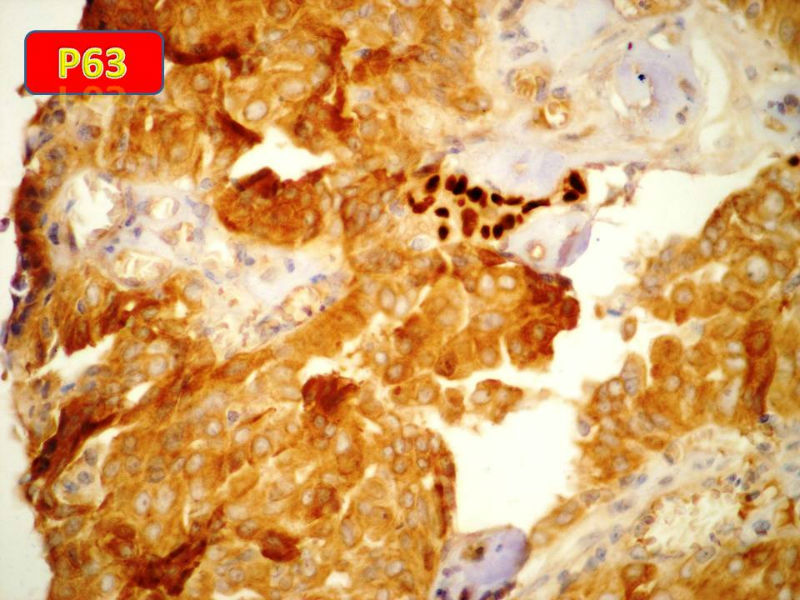

男性,84岁,乳头溢液,流血3个月,送检为乳头内挤出物。

乳腺导管内乳头状瘤